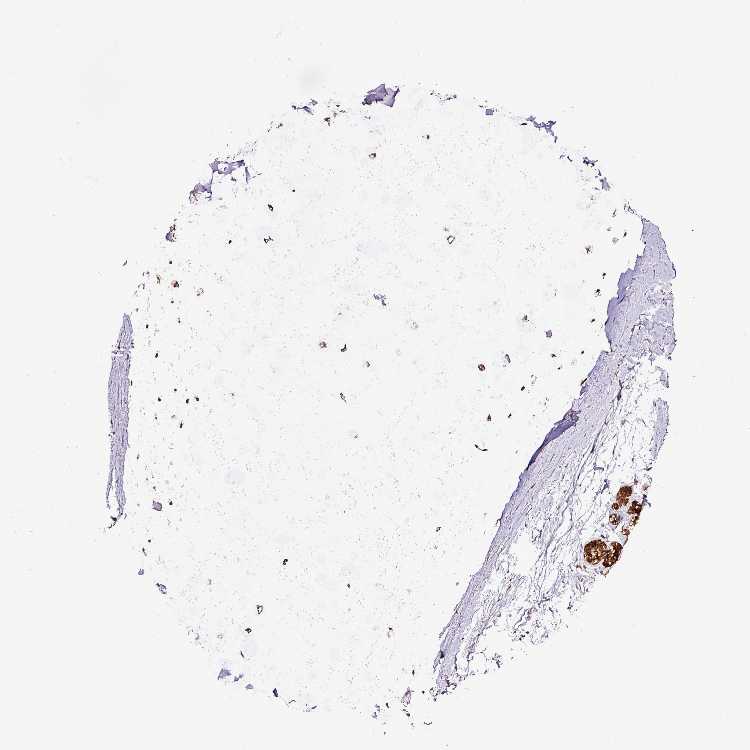

SOFT TISSUE 1 - Antibody stainingi

Antibody staining in the annotated cell types in the current human tissue is reported as not detected, low, medium, or high, based on conventional immunohistochemistry profiling in selected tissues. This score is based on the combination of the staining intensity and fraction of stained cells.

Each image is clickable and will lead to virtual microscopy that enables deeper exploration of all samples and also displays staining intensity scores, fraction scores and subcellular localization as well as patient and tissue information for each sample.

Antibody HPA041120

Chondrocytes Low

Fibroblasts Medium

Peripheral nerve Medium

SOFT TISSUE 2 - Antibody stainingi